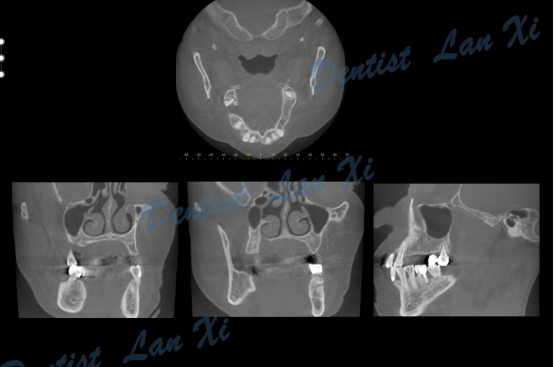

第一步:数据采集(口扫或仓扫+CBCT

第二步:数据匹配

(CBCT采集的Dicom数据与口扫获取的STL数据进行匹配,通过牙齿位点进行匹配。)